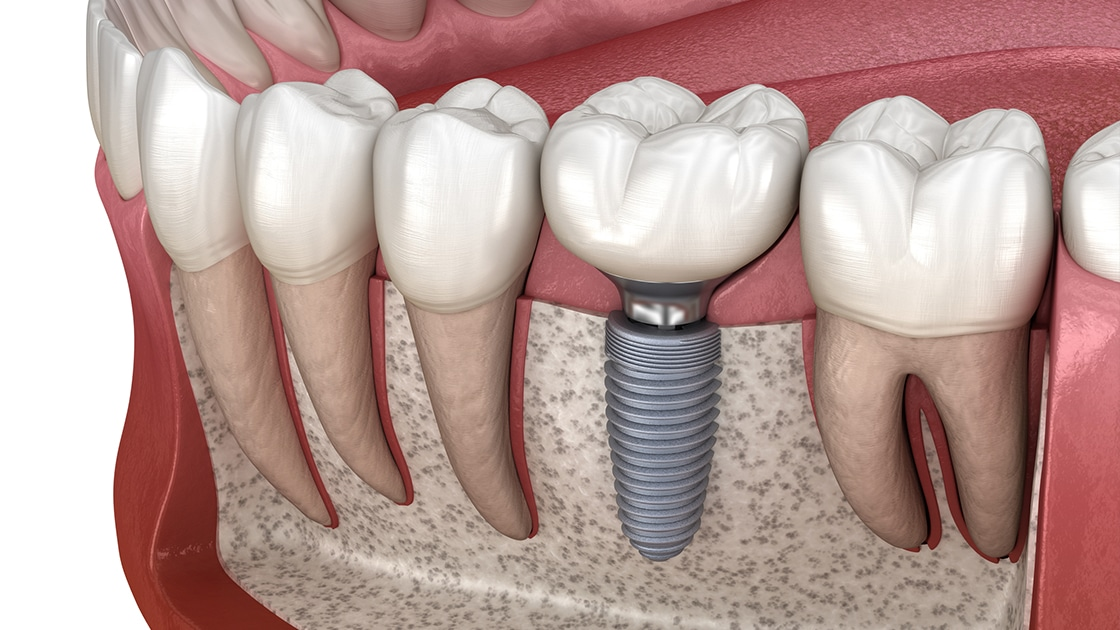

Блять, пару лет назад когда ставил имплант на 5 зуб, мне врач сказал чтобы я удалял нахуй нижнюю восьмёрку, иначе пизда будет рано или поздно. Ну а я хуй забил разумеется.

И это произошло на прошлой неделе. Сначала нестерпимая боль на ночь глядя, всякие ибупрофены не помогли. В итоге бессонная ночь и дикий ахуй утром. Ещё и температура скакать начала. Работать не смог, побежал по стоматологиям.